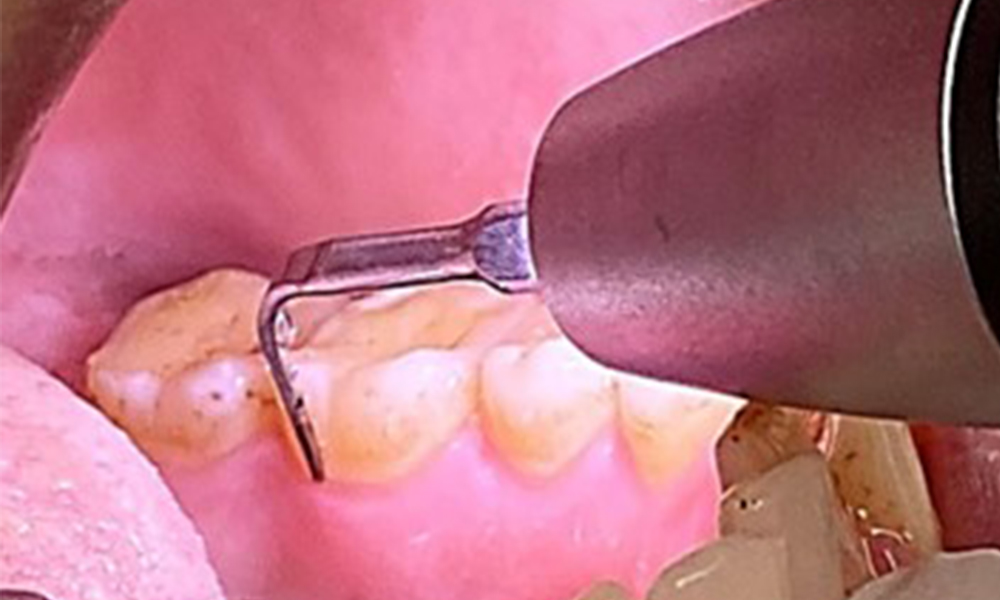

Zugleich ist es notwendig die Interdentalraumbürstchen, welche der

Patient täglich verwendet nach der richtigen Größe zu überprüfen und den Patienten zu bestärken diese konsequent zu benutzen (Abb. 9). Eine

gute Mundhygiene ist unabdingbar, um das Parodontitisrisiko durch das Rauchen zu minimieren.

Anwendung der Interdentalbürstchen in Rg 44/45

Abb. 9: Anwendung der Interdentalbürstchen in Rg 44/45, © Dr. R. Krapf